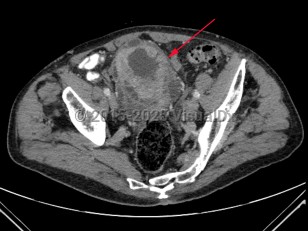

Bladder cancer

Risk factors for development of bladder carcinoma include advancing age, male sex, being of Northern European descent, and cigarette smoking. Occupations with exposures linked to increased risk of bladder cancer include metal workers, painters, leather workers, miners, excavating-machine operators, and manufacturers of carpets, paints, plastics, and industrial chemicals.

Treatment options depend on depth of tumor invasion and presence or absence of metastatic disease. Transurethral resection of bladder tumor (TURBT) may be combined with adjuvant chemotherapy for early-stage disease with radical cystectomy and/or chemotherapy in late-stage disease.